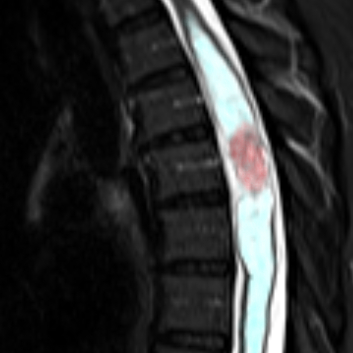

Spinal Cord Tumors

Surgical Treatment